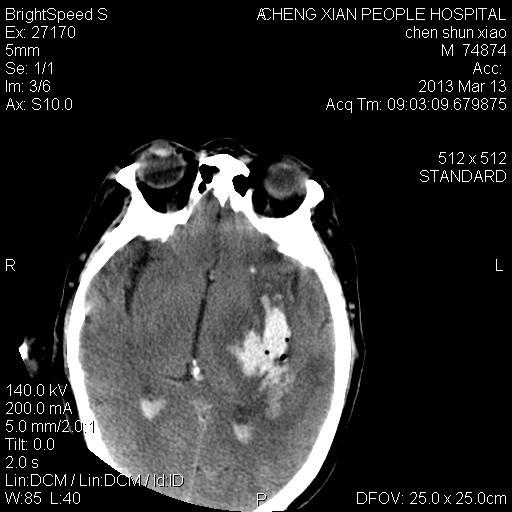

患者陈++,男,71岁。因“昏迷四小时,伴右侧肢体活动受限”以“脑出血”收住院。发病后12小时用“改良立体定向-软通道微创介入新技术治疗脑出血”。术后24小时颅内出血大部被清除,患者神志清晰。右侧肢体肌力0级。

患者陈++,男,71岁。因“昏迷四小时,伴右侧肢体活动受限”以“脑出血”收住院。发病后12小时用“改良立体定向-软通道微创介入新技术治疗脑出血”。术后24小时颅内出血大部被清除,患者神志清晰。右侧肢体肌力0级。